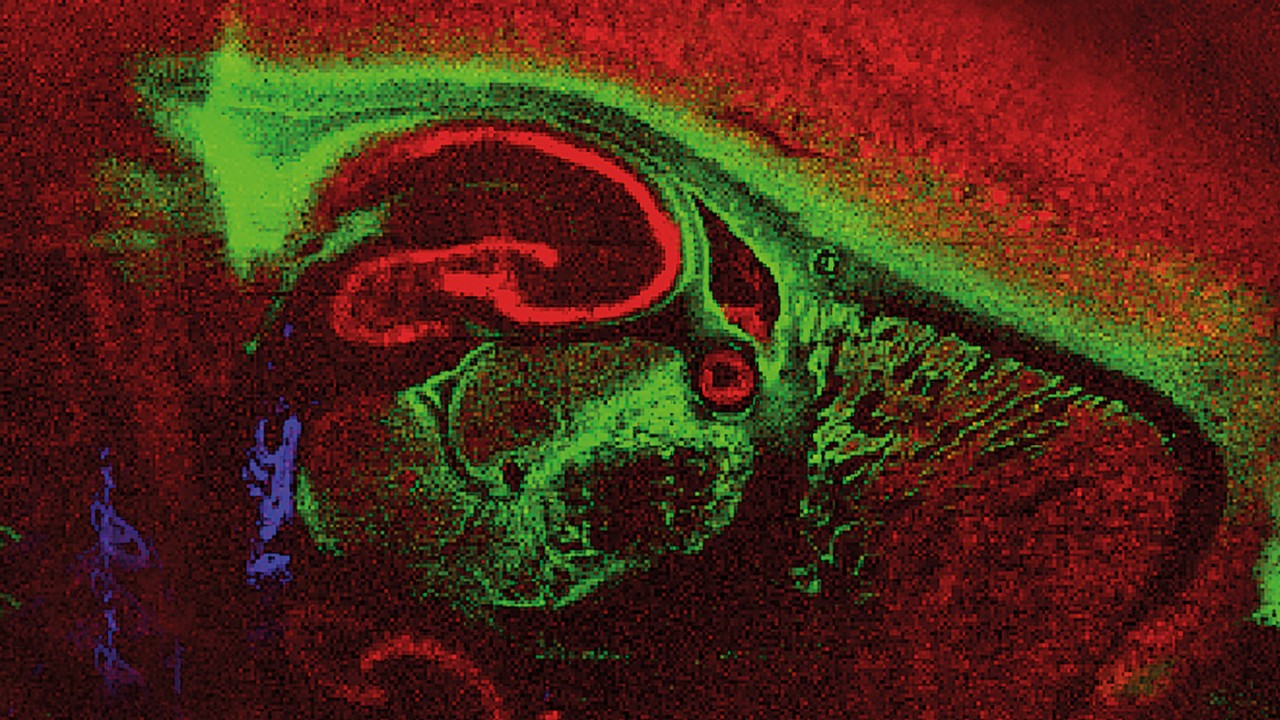

Innovations such as Trapped Ion Mobility (TIMS), smartbeam and scanning lasers for MALDI-MS Imaging that deliver true pixel fidelity, and eXtreme Resolution FTMS (XR) technology capable to reveal Isotopic Fine Structure (IFS) signatures are pushing scientific exploration to new heights. Our mass spectrometry solutions enable scientists to make breakthrough discoveries and gain deeper insights.

Bruker's product lines include the following technologies: timsTOF, MRMS, rapifleX® MALDI-TOF/TOF, UHR-QTOF, Triple Quadrupole, HDX Solution, Toxtyper® and TargetScreener HR. Our industry leading software solutions such as SCiLS™ Lab for MS Imaging, MetaboScape® and Biopharma Compass® are examples for our solutions doing the work for you.